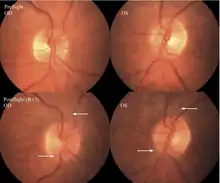

The first U.S. case of visual changes observed on orbit was reported by a long-duration astronaut that noticed a marked decrease in near-visual acuity throughout his mission on board the ISS, but at no time reported headaches, transient visual obscurations, pulsatile tinnitus or diplopia (double vision). His postflight fundus examination (Figure 1) revealed choroidal folds below the optic disc and a single cotton-wool spot in the inferior arcade of the right eye. The acquired choroidal folds gradually improved, but were still present 3 year postflight. The left eye examination was normal. There was no documented evidence of optic-disc edema in either eye. Brain MRI, lumbar puncture, and OCT were not performed preflight or postflight on this astronaut.[5]

The third case of visual changes while on board the ISS had no changes in visual acuity and no complaints of headaches, transient visual obscurations, diplopia or pulsatile tinnitus during the mission. Upon return to Earth, no eye issues were reported by the astronaut at landing. Fundus examination revealed bilateral, asymmetrical disc edema. There was no evidence of choroidal folds or cotton-wool spots, but a small hemorrhage was observed below the optic dics in the right eye. This astronaut had the most pronounced optic-disc edema of all astronauts reported to date, but had no choroidal folds, globe flattening or hyperopic shift. At 10 days post landing, an MRI of the brain and eyes was normal, but there appeared to be a mild increase in CSF signal around the right optic nerve.[5]

The sixth case of visual changes of an ISS astronaut was reported after return to Earth from a 6-month mission. When he noticed that his far vision was clearer through his reading glasses. A fundus examination performed 3 weeks postflight documented a grade 1 nasal optic-disc edema in the right eye only. There was no evidence of disc edema in the left eye or choroidal folds in either eye (Figure 13). MRI of the brain and eyes days postflight revealed bilateral flattening of the posterior globe, right greater than left, and a mildly distended right optic nerve sheath. There was also evidence of optic-disc edema in the right eye. A fundus examination postflight revealed a "new onset" cotton-wool spot in the left eye. This was not observed in the fundus photographs taken 3 weeks postflight.[5]

The seventh case of visual changes associated with spaceflight is significant in that it was eventually treated postflight. Approximately 2 months into the ISS mission, the astronaut reported a progressive decrease in his near and far acuity in both eyes. The ISS cabin pressure, CO2 and O2 levels were reported to be within normal operating limits and the astronaut was not exposed to any toxic substances. He never experienced losses in subjective best-corrected acuity, color vision or stereopsis. A fundus examination revealed a grade 1 bilateral optic-disc edema and choroidal folds (Figure 15).[5]

Optic-disc edema will be graded based on the Frisén Scale[48] as below:

Stage 0 – Normal Optic-disc

Blurring of nasal, superior and inferior poles in inverse proportion to disc diameter. Radial nerve fiber layer (NFL) without NFL tortuosity. Rare obscuration of a major blood vessel, usually on the upper pole.

Stage 1 – Very early optic-disc edema

Obscuration of the nasal border of the disc. No elevation of the disc borders. Disruption of the normal radial NFL arrangement with grayish opacity accentuating nerve fiber layer bundles. Normal temporal disc margin. Subtle grayish halo with temporal gap (best seen with indirect ophthalmoscopy). Concentric or radial retrochoroidal folds.

Stage 2 – Early optic-disc edema

Obscuration of all borders. Elevation of the nasal border. Complete peripapillary halo.

Stage 3 – Moderate optic-disc edema

Obscurations of all borders. Increased diameter of ONH. Obscuration of one or more segments of major blood vessels leaving the disc. Peripapillary halo – irregular outer fringe with finger-like extensions.

Stage 4 – Marked optic-disc edema

Elevation of the entire nerve head. Obscuration of all borders. Peripapillary halo. Total obscuration on the disc of a segment of a major vessel.

Stage 5 – Severe optic-disc edema

Dome-shaped protrusions representing anterior expansion of the ONG. Peripapillary halo is narrow and smoothly demarcated. Total obscuration of a segment of a major blood vessel may or may not be present. Obliteration of the optic cup.